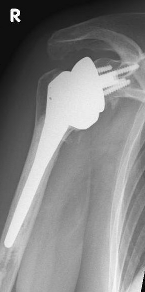

Abbildung7Abbildung8

Short stem prostheses as modern implants for omarthrosis and acetabular wear

left: X-ray image of a short-shaft prosthesis

right: Short-shaft prosthesis (Affinis Short type, Mathys company)